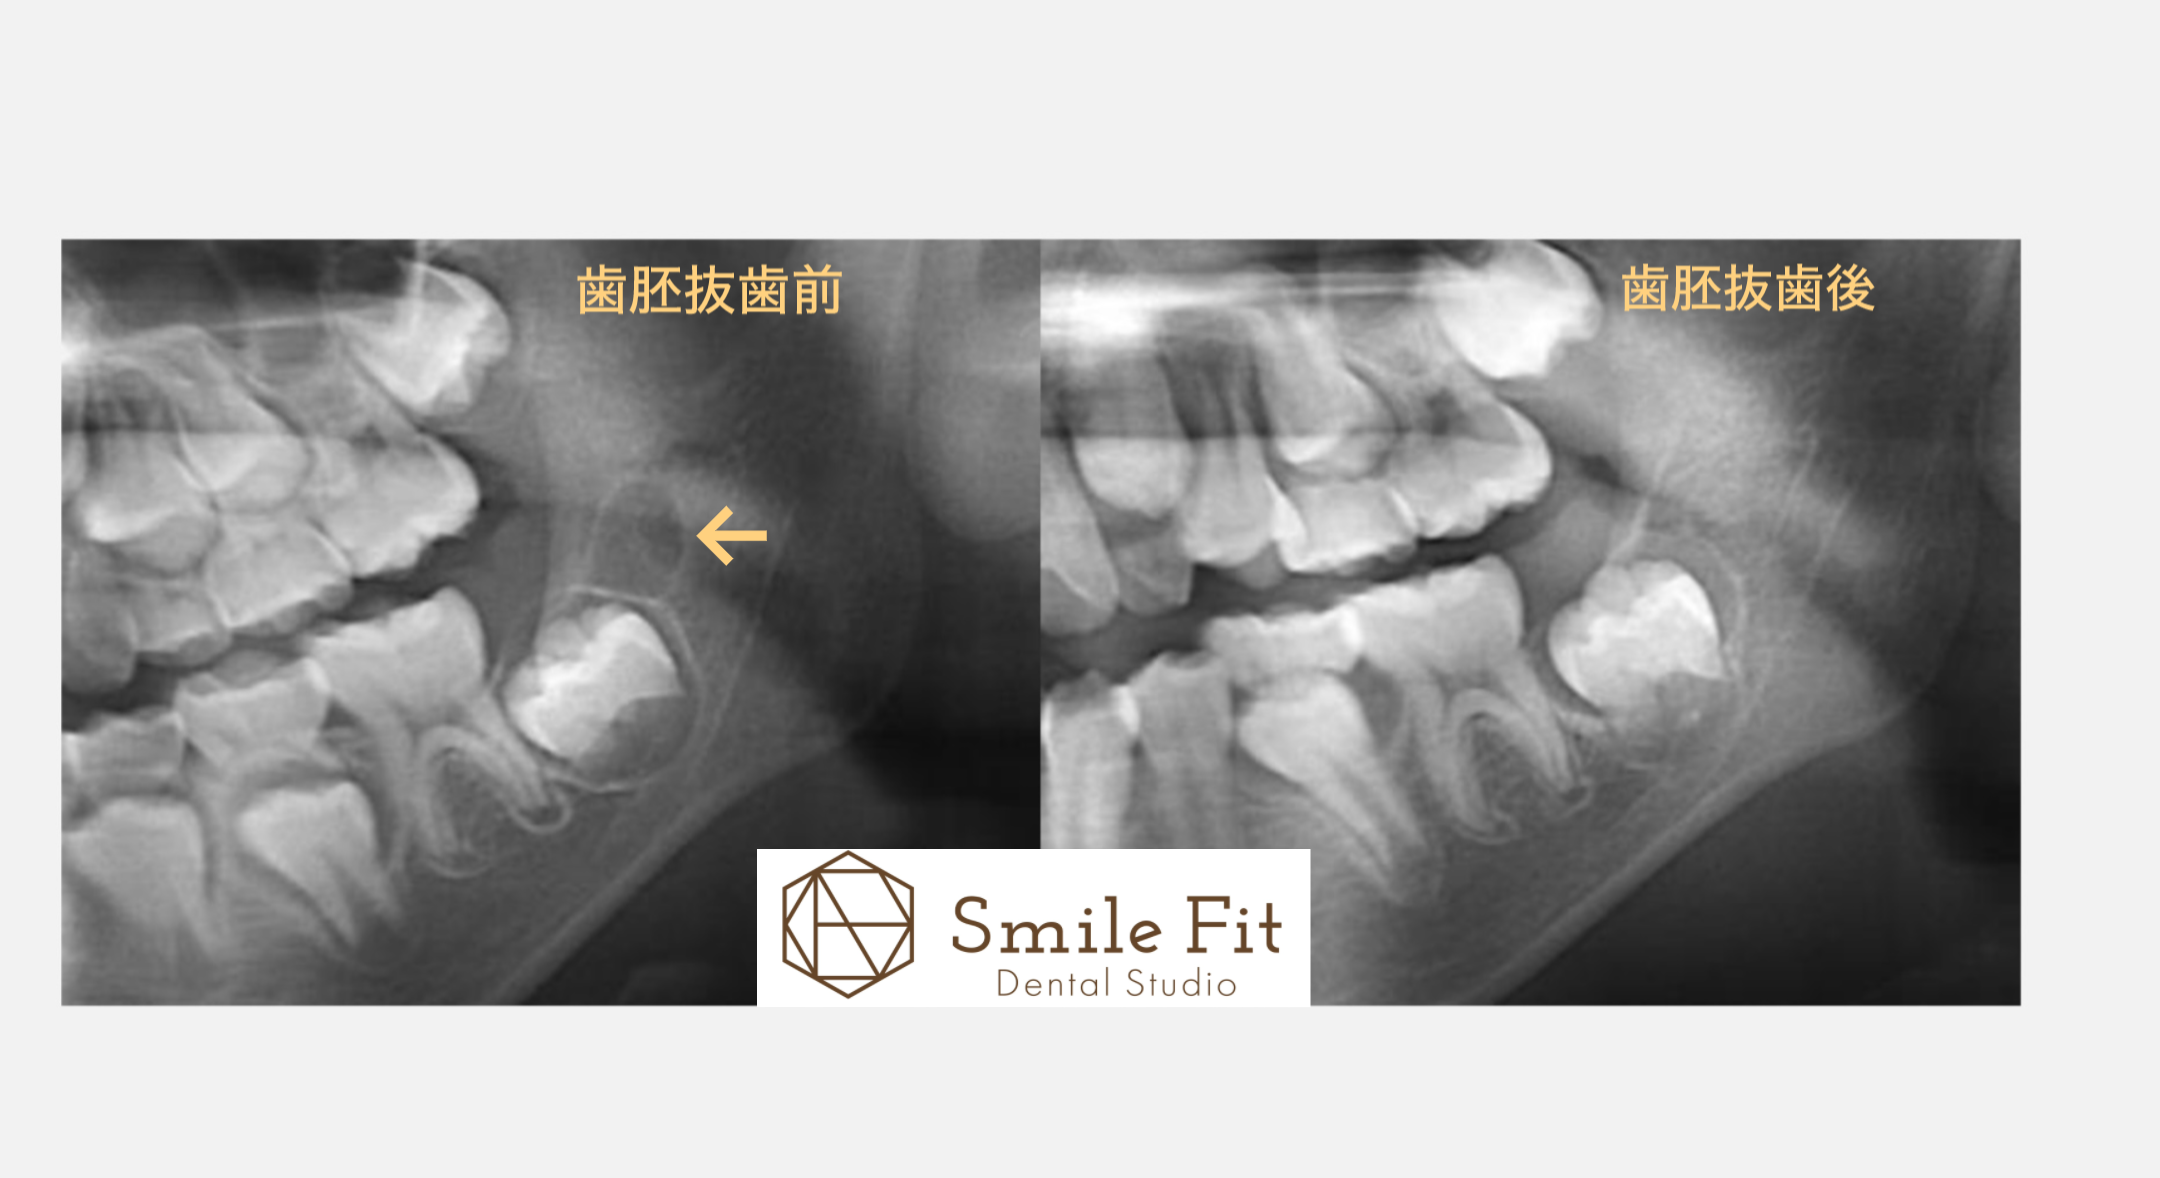

歯胚抜歯とは?将来の歯並びを守るために知っておきたいこと|Smile Fit Dental Studio祐天寺

歯胚抜歯(しはいばっし)